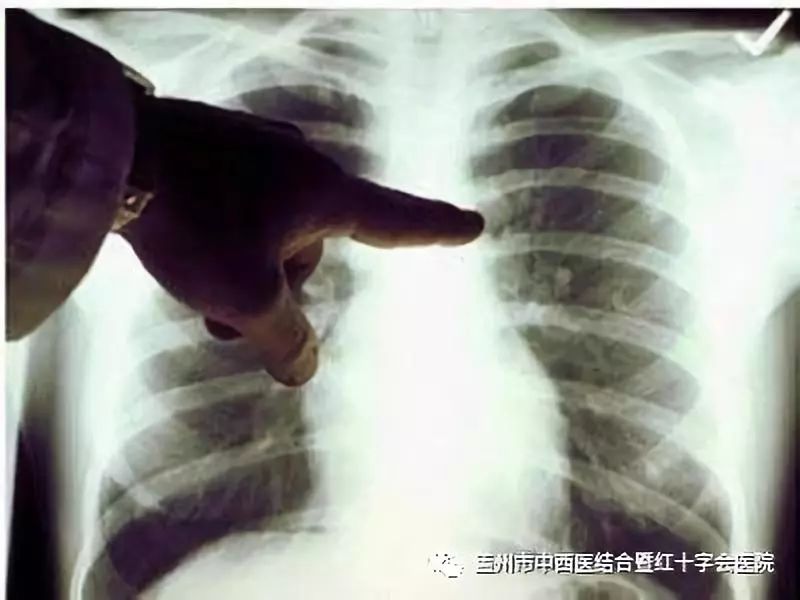

案例:患者 66岁 数月前在家感到身体不适,伴有咳嗽现象,身体消瘦。

于今年2月前往某医院就诊,到院后该院为患者进行CT检查后,初步诊断为肺部炎症,患者回家自行治疗。经数月后不见好转,再次到我市另一家医院就诊,同样进行CT检查再次诊断为肺部炎症,经数月治疗不见好转,期间咳嗽带血,病情加重。

辗转数月数家医院后,来到盖州中西医结合医院就诊通过CT检查,经我院影像科主任李彦曾教授诊断为肺癌,并进行增强肺部CT进一步确认。

此患者由于病情发展发现较晚,又因四处投医而无对症治疗,错过了最佳治疗时机,患者状况不容乐观已形成癌症播散转移。